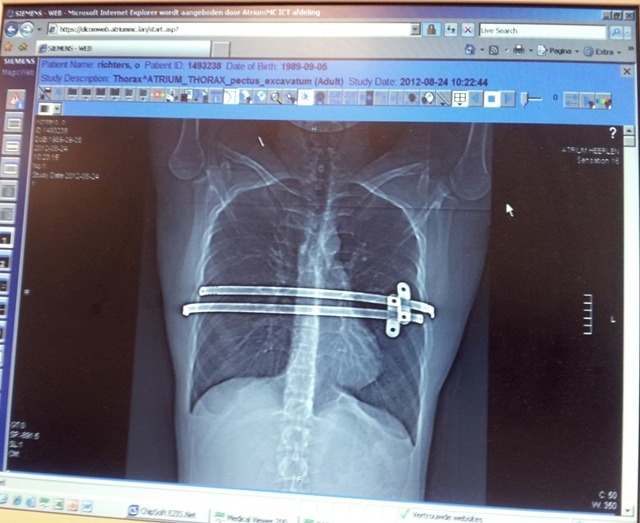

선천적인 오목가슴 기형을 가지고 있었던 올리비에는 어릴적부터 성격이 내성적이었고

그리고 자신을 평생 괴롭혀 왔던 오목가슴 수술을 결심.

심각했던 오목가슴

수술을 마치고 다시 운동 시작.